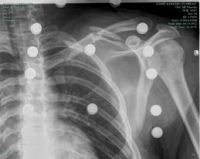

Mit voller Vorfreude und genügend Training startete ich im April in Trophje zum Slowenischen Cup. Am Freitag beim Training fühlte ich mit fit für den Seeding Run. Mit einem technischen Defekt am Samstag zog sich die Pechsträhne fort, als ich am Sonntag im Training stürzte und mir mein Schlüsselbein zertrümmerte.